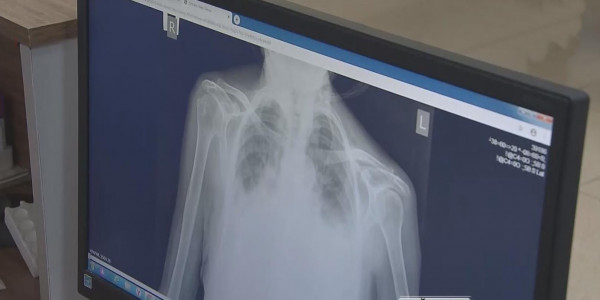

Туберкулез : соңғы жаңалықтар

Жылда жер бетінде 10 миллион адам осы дертке шалдығып, миллиондаған науқас індеттен көз жұмады.